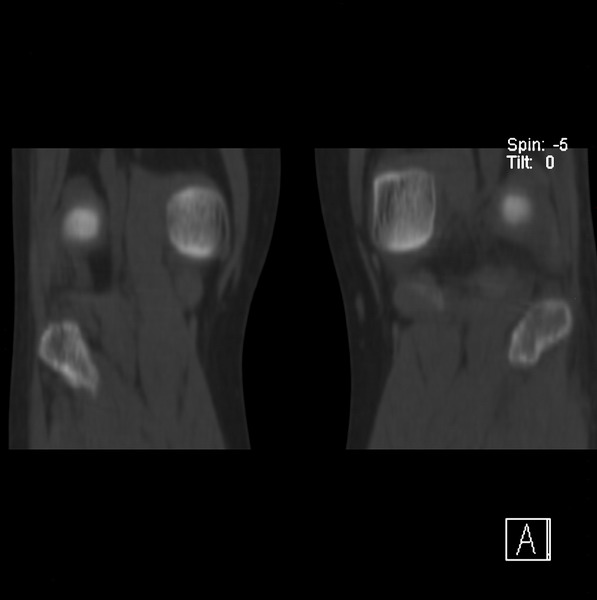

标题: CT21917:右腓骨小头是否骨软骨瘤? [打印本页]

标题: CT21917:右腓骨小头是否骨软骨瘤?

女、43.

不是骨软骨瘤,“牵拽征”,正常变异。有平片吗?

正常变异,“牵拽征”,比目鱼肌牵拽.

比目鱼肌附着点

支持 “牵拽征”——比目鱼肌牵拽。